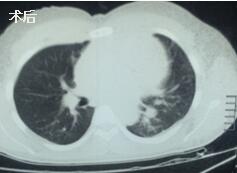

當(dāng)看到病人的CT等外院各項(xiàng)檢查時(shí),我頭皮發(fā)麻,心頭發(fā)怵:巨大的腫塊占據(jù)著整個縱隔,壓迫心臟,與血管關(guān)系密切,初步考慮侵襲性胸腺瘤、胸腺癌或淋巴瘤等,合并腎功能不全,無法完整切除,手術(shù)風(fēng)險(xiǎn)大,手術(shù)并不能提高病人長期生存率,換言之,小伙子等待的是生命的立即終結(jié)。

當(dāng)看到病人癥狀緩解,復(fù)查胸部CT幾近完美,我們那種自豪感油然而生。偶爾去治愈,常常去幫助,總是去安慰,我們深知,小伙子的人生之路并不長,只能深深祈禱他在我們的治療下能走得更遠(yuǎn)一些,能把剩下的日子走的更充實(shí)一些。而我們在能夠幫助人的時(shí)候,別一味地去安慰,永不言棄,是我們這一群胸外人堅(jiān)貞的信念。